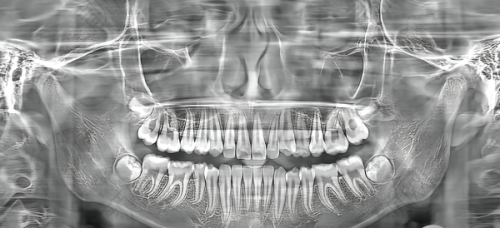

医院开展的项目齐全,涵盖了多个领域。种植牙是重点科室,开展即刻种植、微创种植、All - on - 4/6全口种植等高难度技术,合作进口品牌如瑞典诺贝尔、瑞士ITI等,特邀中韩医生团队联合诊疗,尤其擅长骨量不足患者的种植修复。牙齿矫正提供金属托槽矫正、隐形矫正(隐适美/时代天使)、舌侧矫正等,数字化模拟矫正结果,更准定制方案,儿童早期干预矫治(MRC肌功能训练)也备受家长好评。美学修复包括超薄瓷贴面、全瓷牙冠、牙齿美白(冷光/皓齿美白),注重自然美学设计,打造明星同款笑容。牙周治疗与儿童齿科开展激光牙周治疗、儿童防龋涂氟、窝沟封闭、舒适拔牙等,配备儿童专属诊室和趣味动画播放,缓解孩子看牙恐惧。